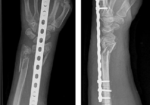

En la maleza – Se analizaron pacientes (n=35) con dedo en gatillo (n=43). Se asignaron veintitrés pacientes al grupo de ferulización de la articulación PIP y 20 pacientes al grupo de ferulización de la MCP. Los pacientes usaron la órtesis durante ocho semanas; estas fueron férula MCP para dedo en gatillo, Férula de bloqueo MCP y férula de articulación de pipa.

Se observó una reducción del dolor en ambos grupos, pero la reducción del dolor fue mayor con la ferulización de la articulación PIP en comparación con el grupo de ferulización de la articulación MCP. Solo hubo una mejora significativa en QuickDASH para el grupo de ferulización PIP. Los pacientes usaron la férula de articulación pip significativamente más tiempo durante el día en comparación con el grupo de férula MCP, probablemente debido a una mayor comodidad.

Llevándolo a casa Los hallazgos sugieren que ambas ortesis son efectivas para reducir las puntuaciones QuickDASH, reducir el dolor y mejorar los síntomas generales del dedo en gatillo según la clasificación de Green. Sin embargo, la férula de inmovilización de la articulación de la punta fue mejor para mejorar la función y el cumplimiento.

Justificación de la calificación. Tamaño de muestra pequeño. Se excluyeron todos los pacientes con comorbilidades, lo que limita la generalización del hallazgo. La inmovilización de la articulación PIP en comparación con la MCP permite una mayor función y un mejor cumplimiento. Al inmovilizar el MCP, se limita el agarre intrínseco, que es una necesidad para el funcionamiento. Los autores recomiendan usar la órtesis durante 4 semanas durante 24 horas para reducir los síntomas desencadenantes, seguido de un uso nocturno de la férula durante otras 3-4 semanas.